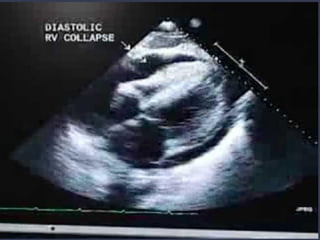

● Este paciente tem SCA, IC, TEP, Tamponamento,

Dissecção???

SIM, NÃO e INCONCLUSIVO